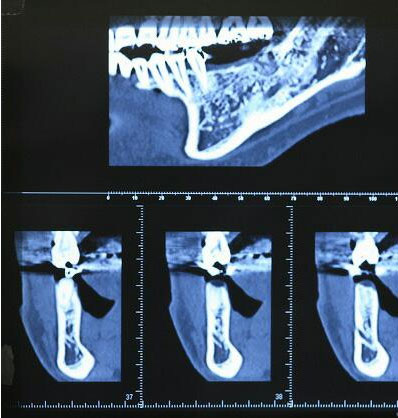

抜歯4ヶ月後のCTエックス線

・真上の写真の楔状の切れ目はオトガイ神経の出口でインプラント埋入手術時は避けなければならない場所です

・このCTレントゲンによってインプラント埋入手術の安全性が大変高まっています

・このCTレントゲンを検討し、インプラント体(フィクスチャー)埋入場所、太さ等を決めていきます